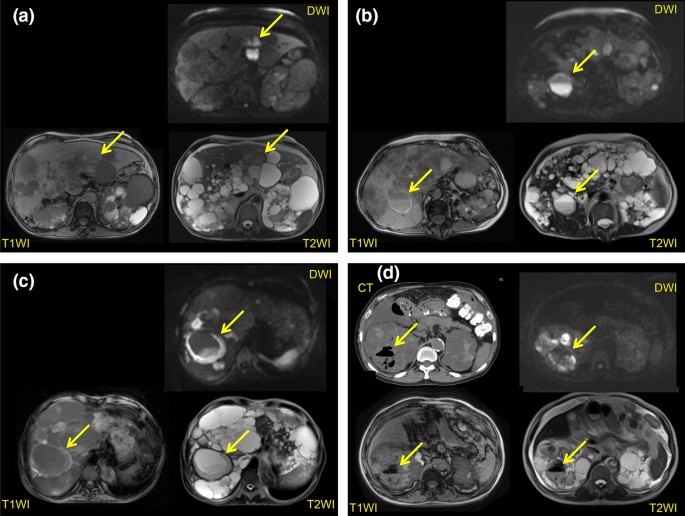

We recently devised MRI diagnostic criteria for cyst infection (Additional file 1) [20]. The possibility of cyst infection can be assessed using our criteria even if causative microorganisms are not identified by culture of the cyst contents [21]. In our criteria, the detection of four intracystic features on abdominal MRI (a high signal intensity [SI] on diffusion-weighted imaging [DWI], fluid-fluid level, wall thickening, and gas) and the assessment of changes over time are important for detecting cyst infection (Fig. 1a–d). The disadvantage of using MRI to detect infected cysts is the low specificity, especially in patients with organomegaly [22]. Intracystic gas is specific for cyst infection, but its sensitivity is only 1.1% (Table 1). A high intracystic SI on DWI showed a sensitivity of 86.4%, but its specificity was relatively low at 33.3% (Tables 2, 3). Both the specificity and sensitivity of a fluid–fluid level and wall thickening were about 80%. However, the specificity of these MRI features decreased as the total liver and kidney volume (TLKV) increased, falling to 65.8% in patients with organomegaly (TLKV > 8500 cm3). A cyst diameter > 5 cm was deemed useful for detecting severely infected cysts that needed drainage, and the specificity was increased by combining it with the other four MRI findings. We concluded that we could identify most cases of severe cyst infection that required drainage by combining the 4 MRI features with abdominal pain at the same location plus changes from previous MRI findings and a cyst diameter >5 cm with almost 100% sensitivity and at least 84.4% specificity.

a MRI findings (T1WI, T2WI, and DWI) in a patient with cyst infection. The infected renal cyst shows a higher intensity on DWI compared with normal cysts, but it is difficult to identify on T1WI and T2WI. b MRI findings (T1WI, T2WI, and DWI) in a patient with cyst infection. A fluid-fluid level and cyst wall thickening can be seen. The infected renal cyst shows a higher intensity on DWI and T1WI than normal cysts, while it has a lower intensity on T2WI. c MRI findings (T1WI, T2WI, and DWI) in a patient with cyst infection. Obvious cyst wall thickening can be seen. The infected cyst is iso-intense on T1WI, T2WI, and DWI. d MRI findings (T1WI, T2WI, and DWI) in a patient with cyst infection. Gas is seen on T1WI, T2WI, and CT. The infected renal cyst shows a higher intensity on DWI compared with normal cysts, while it has a lower intensity on T2WI and T1WI. Sited from Suwabe T, et al. BMC Nephrol. 2016 Nov 9;17(1):170